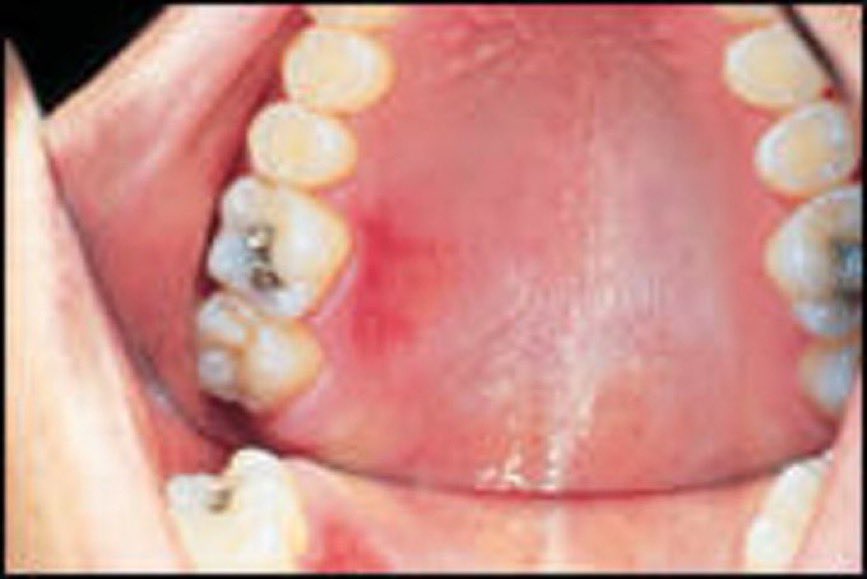

الحروق داخل الفم:

أكلت قطعة قرع حارة بسرعة.. انحرقت لهاتي (سقف الحلق) .. وش سويت؟

حروق الفم تعتبر حروق من الدرجة الأولى، وغالبا تحدث بسبب المأكولات والمشروبات الساخنة جدا.

الجزء المحروق سيفقد الخلايا ويجددها خلال أسبوع وقد يستمر الألم خلال هذا الأسبوع أو يختفي تدريجياً.

حروق اللسان ستختفي أسرع لأن الأوعية الدموية فيه أكثر وفرة..#معلومات_طبية #د_هيفاء_الراشد